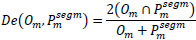

To evaluate the quality of the suggested model segmentation, we employed pixel-level metrics including accuracy, Dice coefficient, IoU, precision, recall, and F1 score. Table 3 represents the definitions of the metrics.

| S.No. | Metrics | Definition |

|---|---|---|

| 1. | Dice Score |

|

| 2. | Accuracy |

[32] [32]ee: True Positives, ff: True Negatives, nn: False Positives, mm: False Negatives |

| 3. | Precision |

|

| 4. | Recall |

|

| 5. | F1-Score |

[33] [33]

|

| 6. | IOU |

|